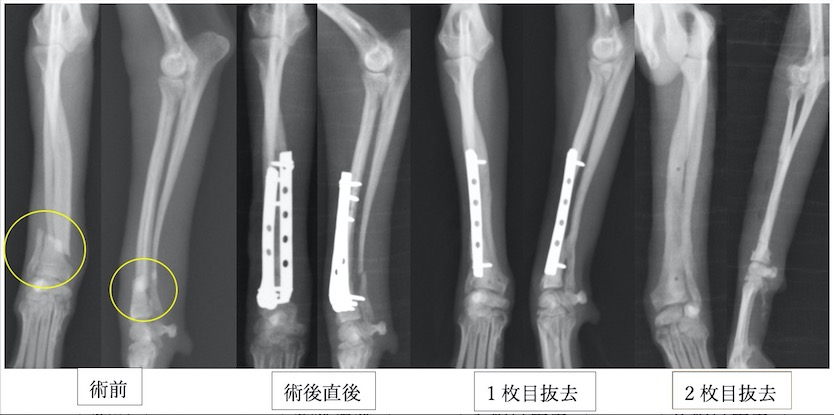

トイプードル2歳の橈尺骨骨折です。1.5mmスクリューを使用しています。

上の3症例ともにやや中央寄りの先端部の橈尺骨の横骨折(遠位骨幹部橈尺骨横骨折)です。直線のプレートを使用しています。